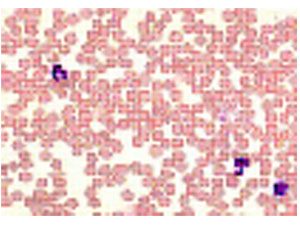

Model: 1092180500Gọi ngay: 0972098096Mã code: 1092180500 Thương hiệu: Merck – ĐứcĐọc tiếpGiemsa’s azur eosin methylene blue solution for microscopy